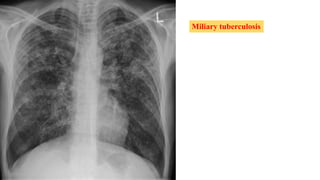

Miliary or Disseminated Tuberculosis

 Miliary tuberculosis is due to hematogenous spread of tubercle bacilli.

 Consequence of primary infection/ reactivation of old disseminated foci.

 The lesions are usually yellowish granulomas 1–2 mm in diameter that resemble

millet seeds (thus the term miliary, coined by nineteenth-century pathologists).

 Fever, night sweats, anorexia, weakness, and weight loss are presenting

symptoms in the majority of cases.

 At times patients have a cough and other respiratory symptoms due to

pulmonary involvement, as well as abdominal symptoms.

 Physical findings include hepatomegaly, splenomegaly, and lymphadenopathy.

 Eye examination may reveal Choroidal tubercles, which are pathognomonic of

miliary tuberculosis, in up to 30% of cases.

Miliary tuberculosis